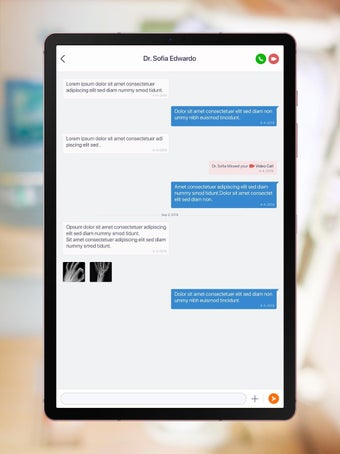

Một trong những tính năng quan trọng nhất của ứng dụng là việc truy cập dữ liệu y tế một chạm dễ dàng. Bệnh nhân có thể truy cập dữ liệu y tế của mình hoặc dữ liệu đại diện gia đình một cách an toàn và nhanh chóng, làm cho nó trở thành một công cụ tuyệt vời để quản lý lịch sử bệnh án của họ. Ứng dụng cũng cho phép người dùng tìm kiếm các phòng khám và bệnh viện gần đó, lên lịch hẹn, và thậm chí nhận chỉ đường đến cuộc hẹn của họ qua Uber. Ngoài ra, bệnh nhân có thể giao tiếp với nhà cung cấp chăm sóc của họ qua tin nhắn an toàn, chia sẻ hình ảnh y tế và cho phép thành viên gia đình truy cập dữ liệu y tế của họ thông qua cài đặt proxy an toàn. Cuối cùng, ứng dụng cung cấp tài liệu giáo dục liên quan đến chăm sóc sức khỏe và có thể kết nối với các thiết bị đeo được hoặc nhập dữ liệu y tế thủ công.